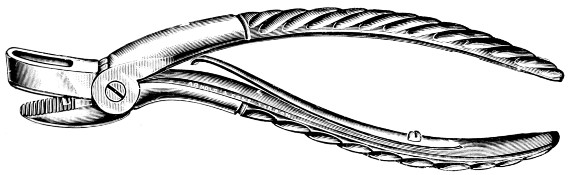

Fig. 13. Keen-Hoffmann’s Craniectomy Forceps.

Fig. 14.

Lane’s Fulcrum

Craniectomy Forceps.

Fig. 15.

Horsley’s Gouge

Forceps.

Fig. 16. De Vilbiss’s Craniectomy Forceps.

Previous to any attempt at enlargement of the trephine hole, the dura mater must be separated from the bone with the aid of Horsley’s dural separator or other suitable instrument. Of the many patterns of craniectomy forceps, the following will be found to suit all requirements:—

The visceral blade is introduced between the dura and the bone and ‘morcellement’ carried out. It is essential[25] that the surgeon should not be too greedy, resting content with the removal of small fragments at a time.

They possess great mechanical advantage and are mainly suited for the rapid removal of large portions of bone.

This instrument is mainly utilized in the smoothing and refreshing of sharp edges of bone, and in the ‘morcellement’ of the thinner portions of the skull—temporal and cerebellar regions.

A clever contrivance whereby the operator is enabled to cut a narrow channel in the bone. Mainly utilized in the formation of the osteoplastic flap.